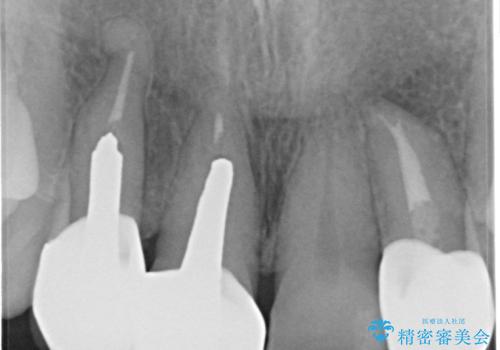

前歯のかぶせもののやり直し、根の治療も

- 前歯のかぶせ物の際が黒いことを気にされて来院。

左上のかぶせ物になっていない歯は根の先に膿がたまっていたので根の治療をし、プラスチックでつぎはぎになっていたためセラミッククラウンでかぶせました。

- 61.6万円 内訳:右上12および左上2(ジルコニアクラウン14万円×3 仮歯1万円×3) 左上2(再根管治療 9万円、ファイバーコア2万円) 費用は治療当時の料金となります

右上12の二本の根の治療は特に行っておらずクラウンのみやり替えを行いました。